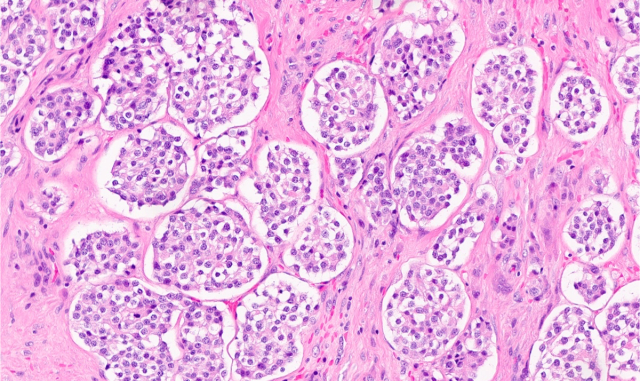

DICER1 syndrome is a genetic disorder associated with an increased risk for developing tumors in the lungs, kidneys, ovaries, thyroid ...